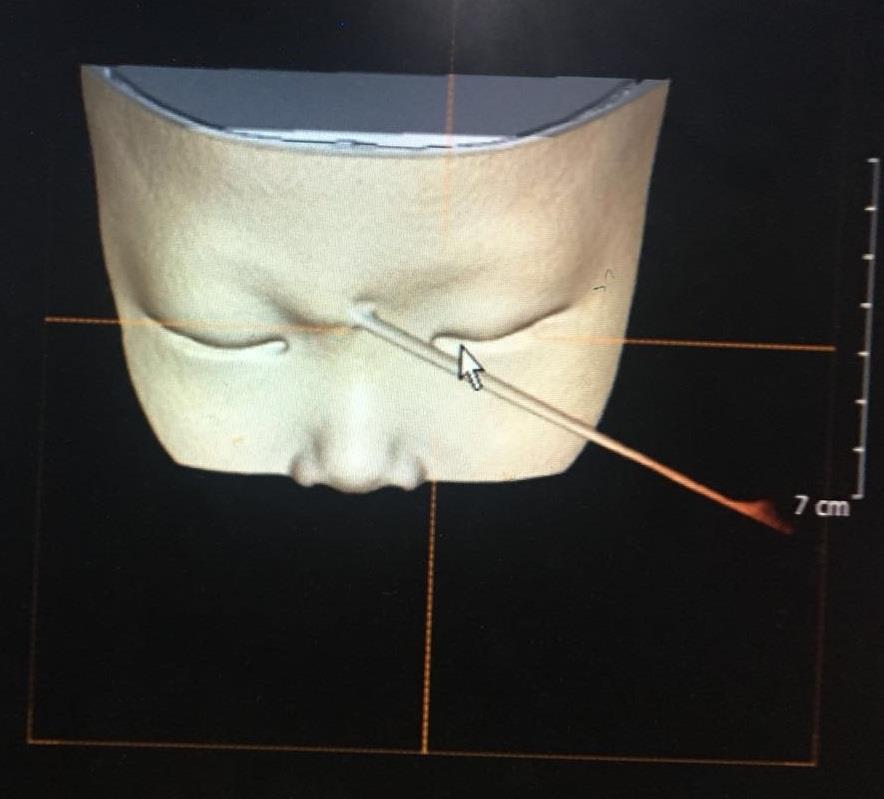

近日,我院眼科收住了一例特殊的小病人。当天下午近五点,一对焦虑而疲惫的夫妻急急地抱着一个明显哭过的小孩来到眼科,小孩2岁,鼻根部近右眼眶一根长长的竹签格外显目,外露的竹签不短,可是接诊医生查屹担心的是戳入的竹签:

幸运的是,经眼眶CT检查后确认竹签从鼻根部进入上眶缘,并未进入颅内,经过上直肌与眼球擦肩而过。然而,怎么取?这是一个问题,外侧竹签长,内侧短,根据杠杆原理,你在外面稍有移动,可能就在里面如秋风扫落叶一般,伤害到重要的血管、神经,甚至,导致失明。正所谓差之毫厘,失之千里,查医师首先建议全麻。然而,2小时前患儿已进食,全麻需禁饮禁食6小时以上。但这个2岁的小朋友在竹签的折磨,越发烦躁,哭闹不安,家属深怕竹签位置在小孩的挣扎下不断地往深处去,造成更大的损伤,强烈要求医生尽早取出竹签。